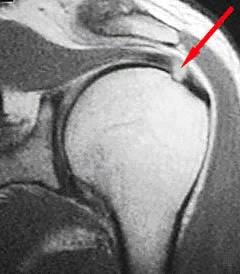

In addition to the types of symptoms experienced by the patient and the physical exam findings, imaging studies are often very useful in diagnosing rotator cuff injuries. Plain radiographs do not show soft tissues particularly well, but indirect evidence seen on plain films often indicates rotator cuff injury. These may include spurring on the undersurface of the acromion or AC joint, cystic changes in the greater tuberosity, calcifications within the rotator cuff, and possibly a high-riding humeral head. The most definitive imaging technique to help with the diagnosis of rotator cuff injuries is magnetic resonance imaging (MRI). A well-done MRI with a high field magnet is typically excellent at determining the presence or absence of tendinosis, partial tearing or full-thickness tearing, and also provides specific information as to the size and location of the injury. It also provides information as to chronicity and reparability of the tear by revealing the extent of atrophy or fatty infiltration of the various rotator cuff muscles.

MRI – normal Rotator Cuff

MRI – Rotator Cuff tear